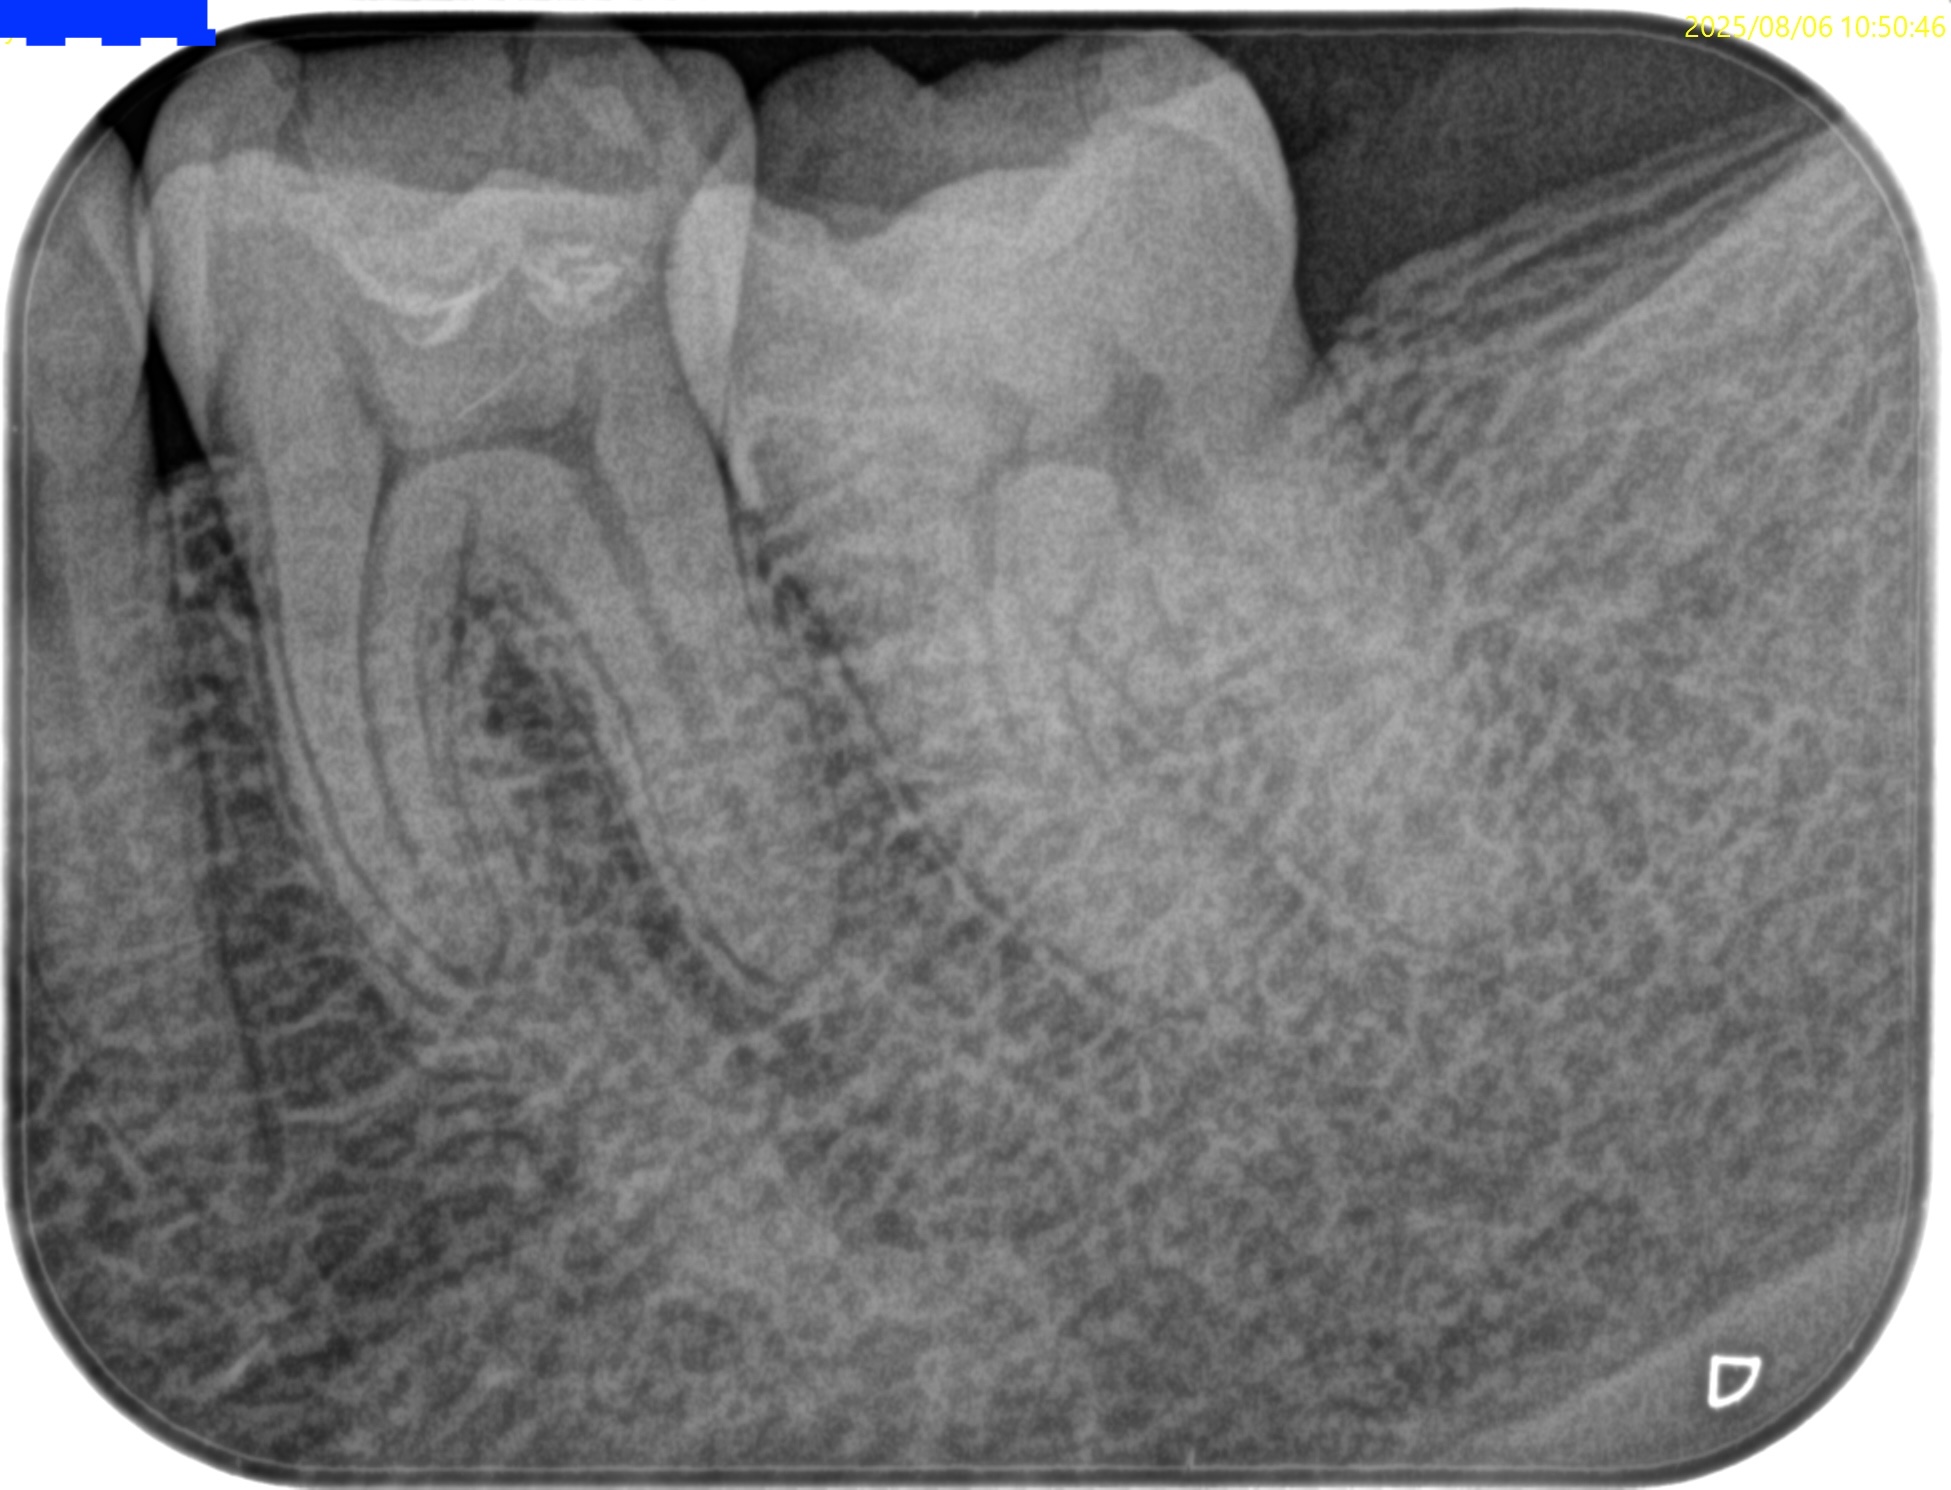

参考ケースは以下だ。

Dにはほぼ歯髄に修復物が覆いかかっている。

これは、

Asymptomatic irreversible pulpitisの可能性が高いだろう。